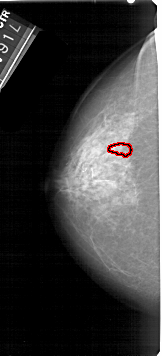

A_1706_1.LEFT_CC

LEFT_CC LINES 5326 PIXELS_PER_LINE 2416 BITS_PER_PIXEL 12 RESOLUTION 43.5 OVERLAY

FILE: A_1706_1.LEFT_CC.OVERLAY

TOTAL_ABNORMALITIES 1

ABNORMALITY 1

LESION_TYPE CALCIFICATION TYPE PLEOMORPHIC DISTRIBUTION CLUSTERED

ASSESSMENT 4

SUBTLETY 1

PATHOLOGY BENIGN

TOTAL_OUTLINES 1

BOUNDARY